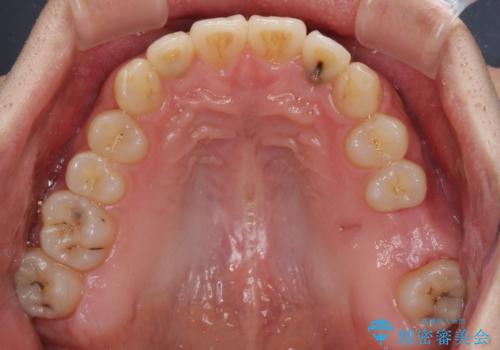

前歯のクロスバイトと抜歯が必要な奥歯の虫歯 インビザラインとインプラント治療

- 前歯のクロスバイトと、大学生のころから放置している虫歯を気にして来院された患者様です。

マウスピースでの矯正治療を希望されていましたが、前歯のクロスバイトは不十分な仕上がりや歯髄壊死などのリスクが高くなるため、術前にワイヤーで大まかに整えてからインビザラインにて矯正治療を行うこととしました。

奥歯の虫歯は抜歯が必要であったので、矯正治療前に抜歯をし、矯正治療と並行してインプラントによる補綴治療を行うこととしました。

当院の特徴は、矯正治療とインプラント補綴治療の担当医が同じ歯科医師であるため、両方の治療を並行して行うことができます。